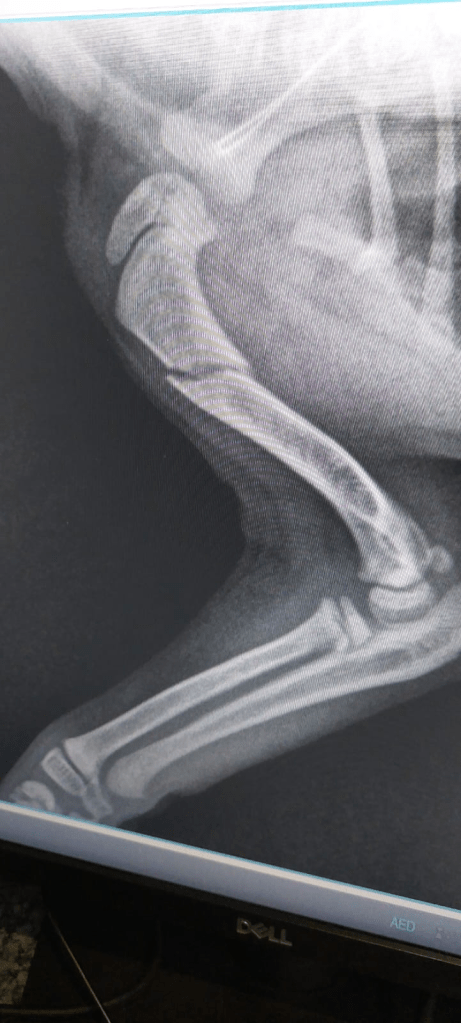

I worried but she stayed safe despite tumbling regularly. Then on Monday we were having horrendous wind storms and when I was moving some items from the front to the back garden, the wind blew the back door very hard and it hit little Poppy from behind, knocking her over onto her back. Then the door was sucked back open by the winds and slammed shut hard against the side of her little body now wedged into the door jamb. She screamed so loudly it almost stopped my heart, I thought she might be dead. I picked her up and held her until she calmed down. We set her down and she could not stand on her right front leg. Norm took her straight down to the vet and they x-rayed her to see that she had broken her right upper leg between the shoulder and the elbow. They booked her in for surgery the following day.

Norm took her to the vet the next morning for her surgery and we picked her up at 4pm. The receptionist said that she yelped so much when in the cage on her own they had to hold her to shut her up. She was wide awake when she and Norm came home. He showed me a copy of an Xray from the vets. It looks like they used a large paper clip.